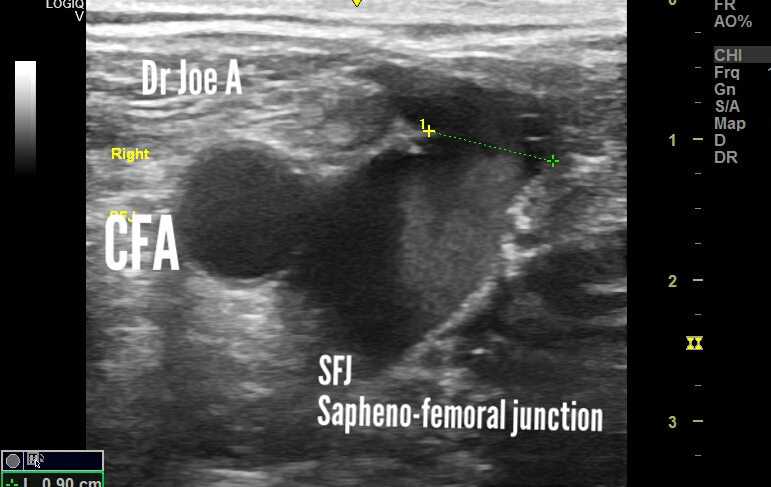

Also B mode ultrasound shows smoke sign of severe turbulence in the SFJ, Sapheno-femoral junction.

The valsalva maneuvere shows more than 3 seconds of reversed flow on spectral Doppler ultrasound in the SFJ.

What is the smoke sign in sapheno-femoral junction incompetence?

Smoke sign is a significant finding on ultrasound imaging of the veins, especially in cases of sapheno-femoral incompetence. It indicates the presence of turbulent blood flow in the veins, which is a hallmark of venous insufficiency.